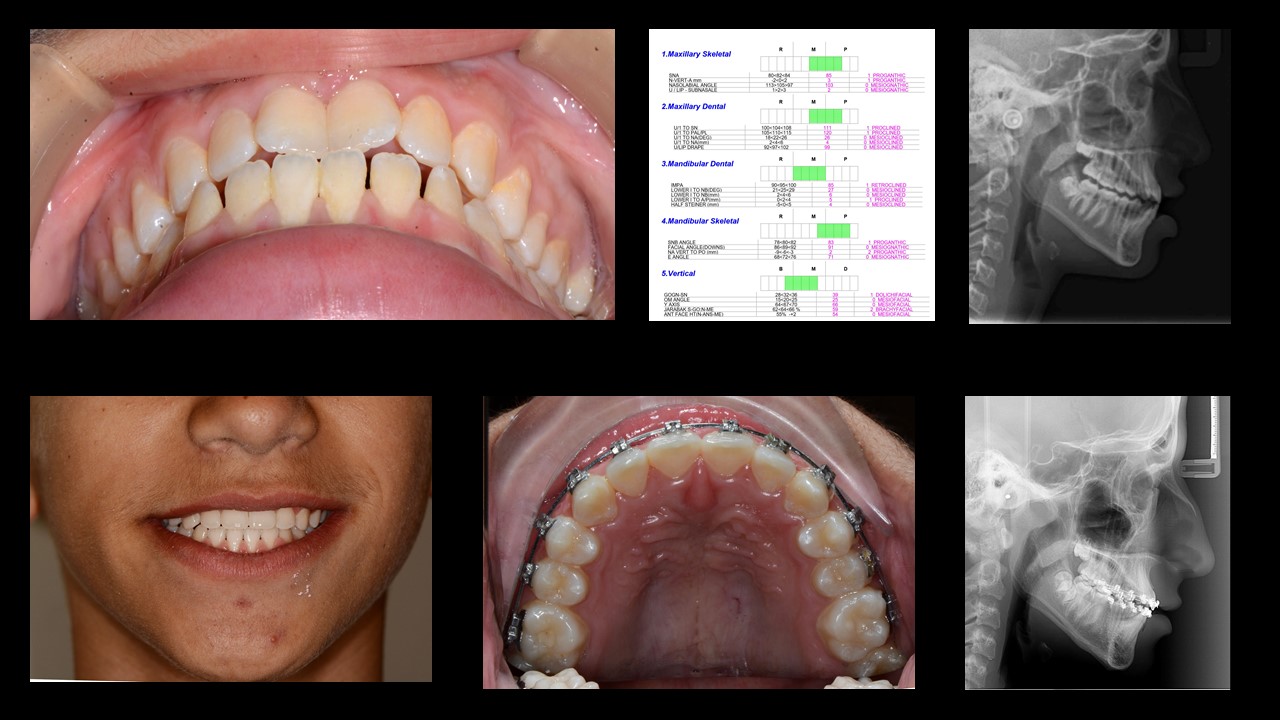

לעיתים קרובות ניתן לטפל בליקוי סגר קל מסוג קלאס III על ידי תיקון דנטלי בלבד שבו מבצעים הטיה קדימה של החותכות העליונות ורטרוקלינציה של החותכות התחתונות, כל עוד תהליכי הגדילה של הלסתות הסתיימו והזווית בין החותכות העליונות והתחתונות אינה חדה מדי.

Mild Class III malocclusion can often be treated with compromise of proclination of upper incisors and retroclination of lower incisors, as long as growth is completed and the inter-incisal angle is not too sharp.